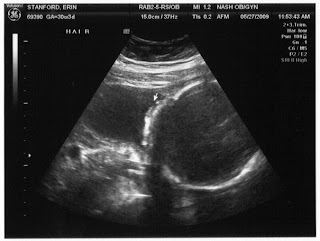

So, it was SO wonderful to get to see our little Caroline again! She is growing bigger and stronger every day! The tech confirmed for us that our little girl is in fact a little girl! That is the first picture below. It is VERY obvious that she is a little girl!!! The second picture is of the hair she already has. Praise the Lord, I haven't had the heartburn that I hear usually comes along with that! The last 2 pictures are profiles of Caroline. She had her face pressed very close to my uterine wall, so the tech wasn't able to get great pictures, but you can see a little bit. SO, the biggest development that came out of our U/S is that Caroline's head is measuring in the 98th percentile. Yikes! They excluded bad things like water on the brain that her having a big head would be an indicator of. David's Mom said that his head was in the 98th percentile when he was born, so like father, like daughter! Poor Caroline! At least they won't be using forceps like they did with him! I have another ultrasound scheduled for July 7th to check on her growth.